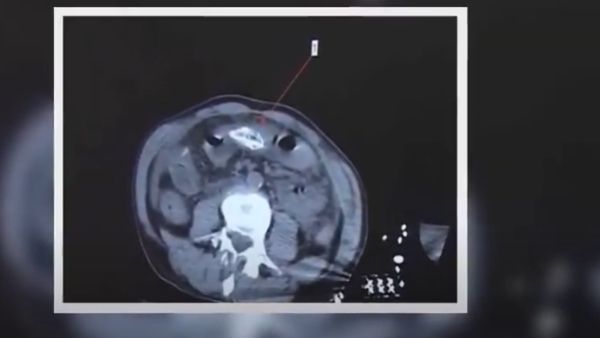

चीनी मीडिया के मुकाबिक पीड़ित शख्स बाजार से 8 ईंच लंबी और हल्की जहरीली माने जाने वाली मछली खरीदकर अपने घर ले गाया और फिर किसी तरह से उसने उसे अपने रेक्टम में मछली को डाल दिया। 8 इंच लंबी ईल मछली रेक्टम में जाने से पहले उसके पेट में फंस गई और पीड़ित शख्स की हालत खराब होने लगी। वो धीरे धीरे दर्द से तड़पने लगा और जब दर्द बर्दाश्त से बाहर चला गया, उसके बाद वो गंभीर हालत में डॉक्टरों के पास पहुंचा। जहां मछली निकालने के लिए डॉक्टरों को उसका ऑपरेशन करना पड़ा।

ऑपरेशन करने वाले डॉक्टरों ने कहा कि मरीज की तबीयत काफी खराब हो गई थी और हेमोलिसिस की वजह से उसकी जान भी जा सकती थी। आपको बता दें कि ये बीमारी तब होती है जब शरीर के अंदर रेड ब्लड सेल्स बर्बाद हो जाते हैं और ऐसा तब होता है जब बड़ी आंत के बैक्टिरिया पेट तक पहुंच जाते हैं। ग्लोबल टाइम्स की रिपोर्ट के मुताबिक पीड़ित मरीज शर्म की वजह से डॉक्टर के पास नहीं जा रहा था, लेकिन जब उसकी स्थिति काफी खराब होने लगी और जब उसे लगने लगा कि अब उसकी जान नहीं बचेगी तो फिर वो फौरन इलाज के लिए अस्पताल पहुंचा। डॉक्टरों के मुताबिक मछली करीब 20 सेंटीमीटर यानि 58 इंच लंबी थी।

डॉक्टरों ने आपातकालीन सर्जरी में मछली को पेट से बाहर निकाल दिया और कहा कि आदमी का पेट काफी संक्रमित हो गया था और अगर थोड़ी देर और हो जाती तो उसका बचना नामुमकिन हो जाता। तीन दिनों तक आईसीयू में रखने के बाद डॉक्टरों ने पीड़ित शख्स को डिस्चार्ज कर दिया। वहीं, चीन ने पिछले साल 68 साल के एक शख्स ने ईल मछली के द्वारा अपनी बवासीर का इलाज करने की कोशिश की थी। माना जा रहा है कि चीन में ईल मछली को लेकर कई तरह के अफवाह हैं और लोग अकसर इस तरह की जानलेवा हरकत करते रहते हैं।